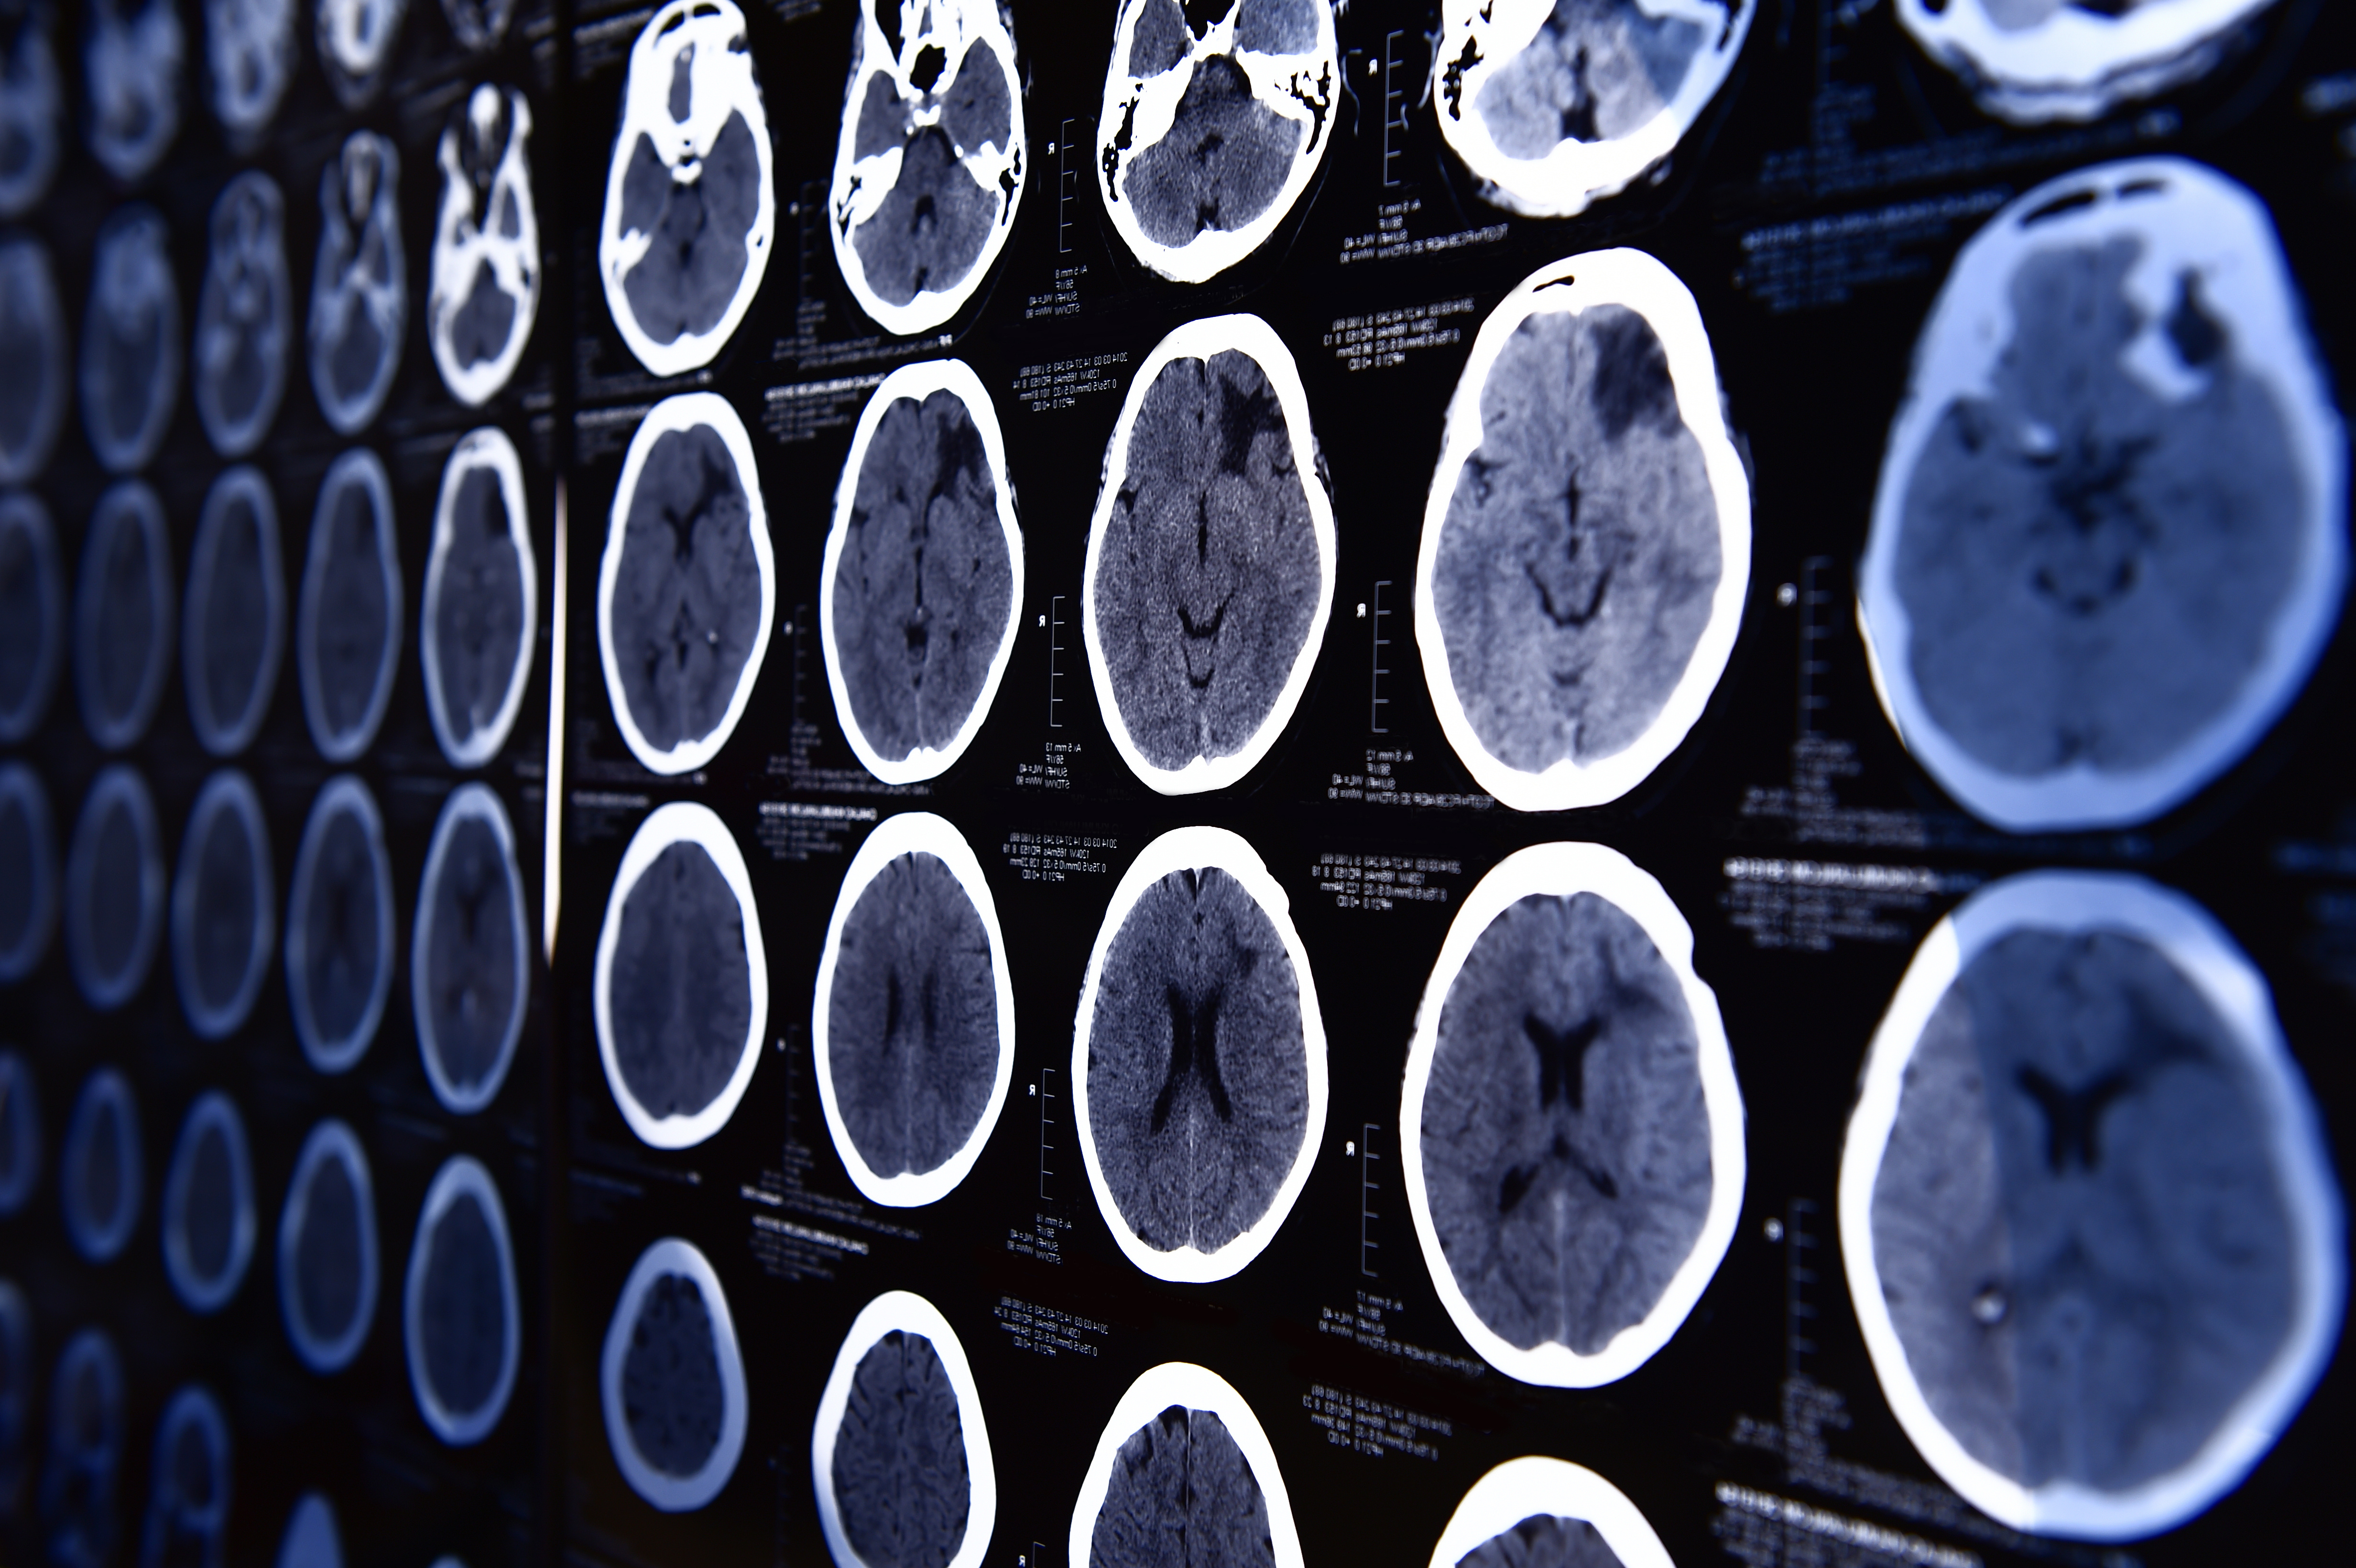

CT use in the emergency department has increased more than 2-fold